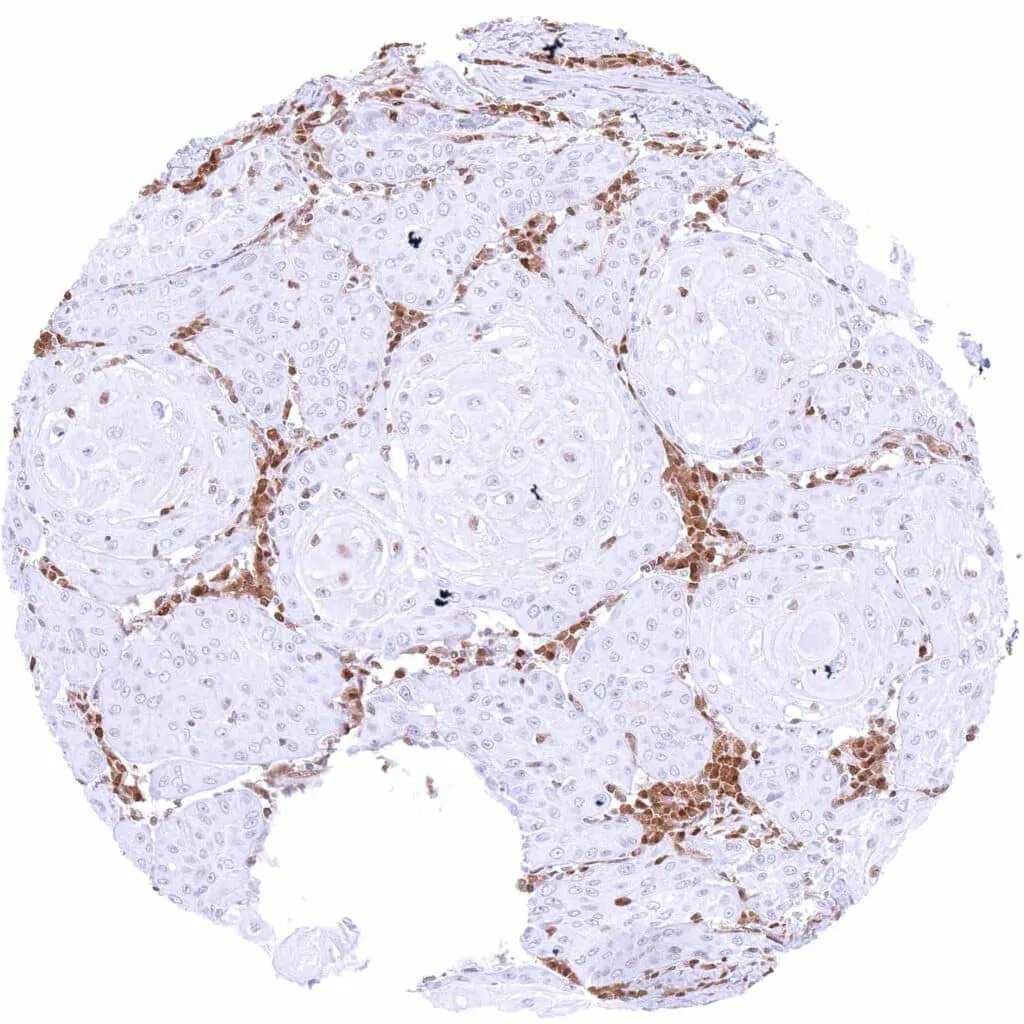

Kidney – Chromophobe renal cell carcinoma with distinct nuclear p27 staining of all tumor cells.